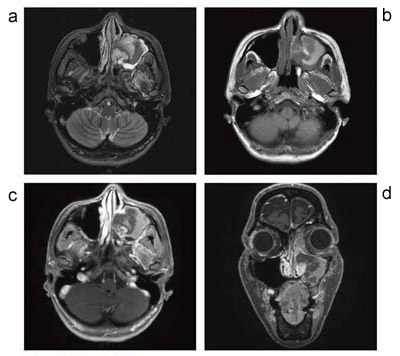

次に,上顎洞腫瘤(図4)であるが,上顎洞周囲の信号が均一であり,眼窩の脂肪抑制効果も非常に良い。本症例では,脂肪抑制Gd-DTPAダイナミック造影検査はIDEALで行っている。矢状断にて3Dでデータ収集を行っており,図4に提示している軸位断像・冠状断像はともに,矢状断で収集したデータからの再構成画像である。IDEALはFSEシーケンスや3D-GRE/SPGRで使用可能であり,局所磁場不均一を克服し,全身制覇を達成したとするGE社の自信にも納得できる画像である。

図4 左上顎洞血瘤腫

a:STIR軸位断像 / b:T1強調画像軸位断像

c:IDEALによる脂肪抑制造影T1強調画像軸位断像(矢状断像からの再構成画像)

d:IDEALによる脂肪抑制造影T1強調画像冠状断像(矢状断像からの再構成画像)